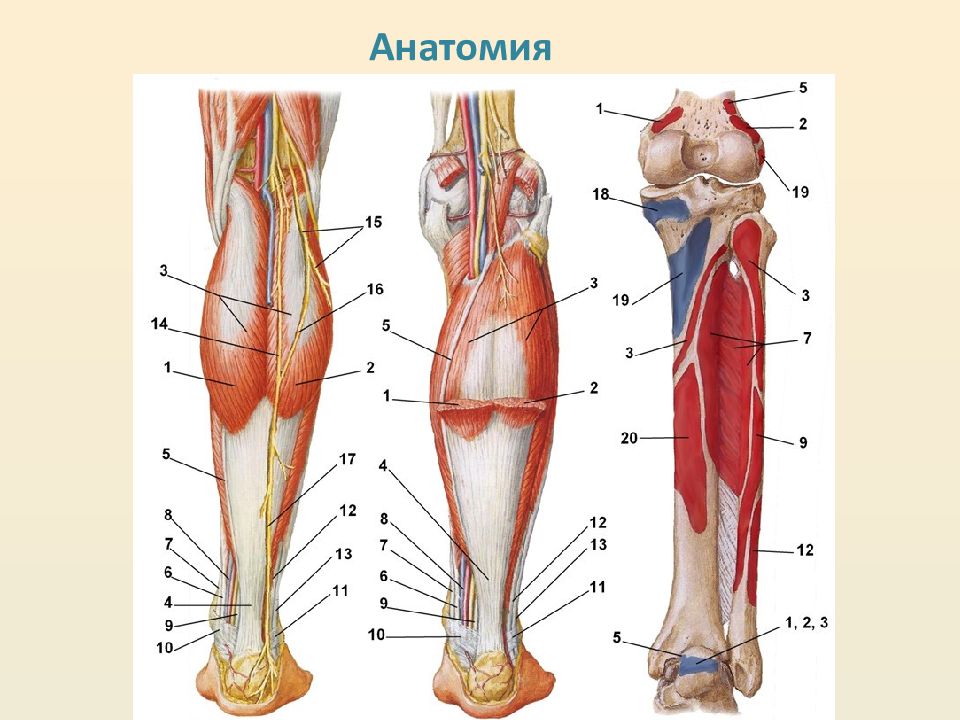

Возможные причины болей в ноге ниже колена и рекомендации